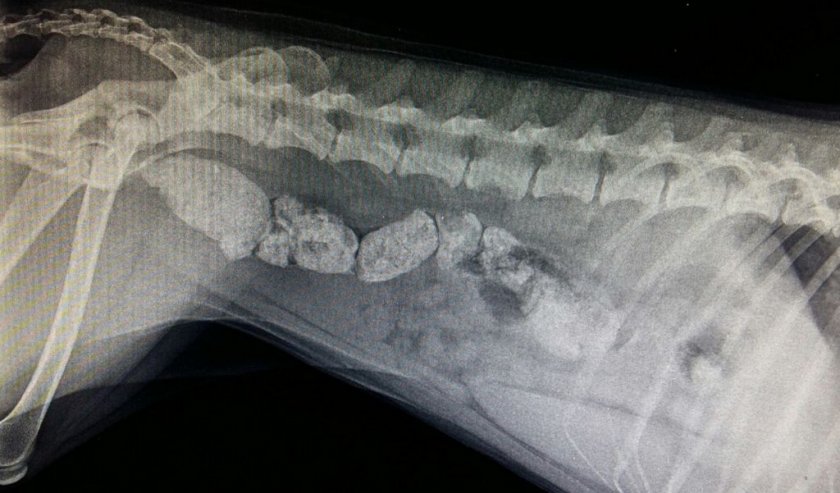

- попавшие в кишечник камни, кости, растения или кусочки игрушек мешают попытке покакать;

Собаки познают мир, пробуя предметы на зуб. Поэтому иногда глотают совершенно несъедобные вещи и это приводит к закупорке (кишечной блокаде). Самый распространённый виновник патологии — кости. Некоторые осколки не полностью перевариваются и тоже могут стать причиной запора.